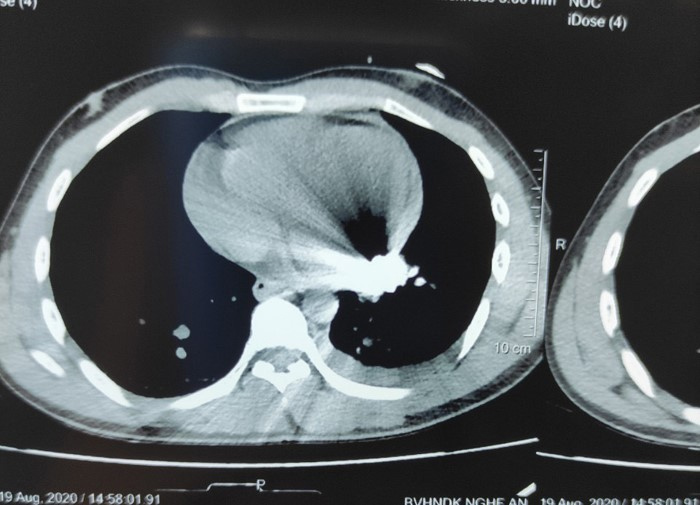

Hình ảnh chụp cắt lớp cho thất dị vật kim khí nằm trong tim bệnh nhân.

Tiến hành siêu âm, các bác sĩ phát hiện tràn dịch màng tim, dịch màng phổi trái. Chụp cắt lớp vi tính, họ phát hiện thêm dị vật kim khí nằm trong màng ngoài tim ở thành sau tâm thất trái.